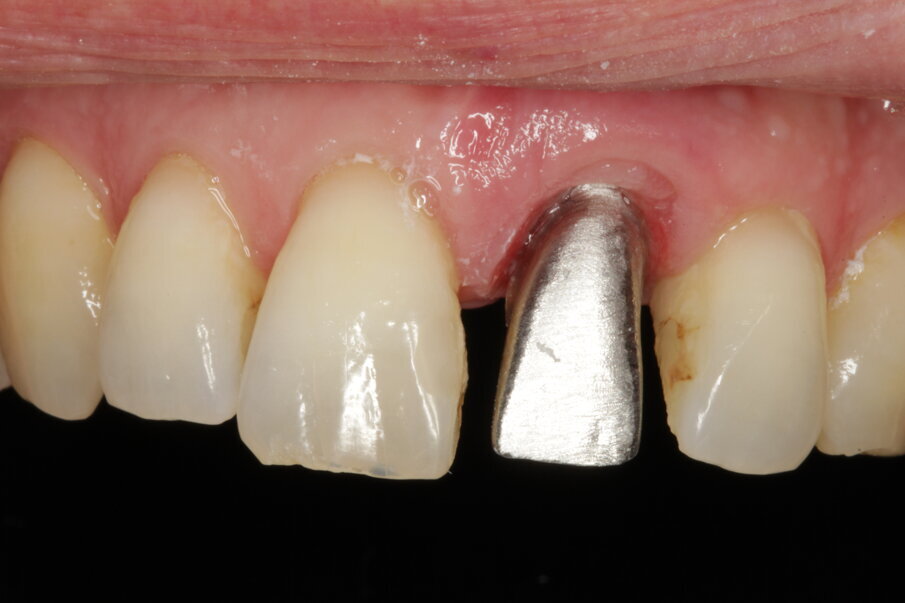

Temporary crown

The surgeon indicated that the healing abutment may be removed after four weeks. By then, the temporary screw-retained crown had already been fabricated by the technician, who had prepared a CAD/CAM-milled acrylic tooth glued on to a Neoss NeoLink abutment (Figs. 27–30). As a result of the decision to place the implant entirely in native bone, the angulation was such as to locate the screw access hole of the provisional on the buccal aspect. This can be easily camouflaged by a simple composite filling after plugging the channel with PTFE tape. The gingival profile copies in this first stage of loading the central incisor anatomy of the Neoss Esthetic Healing Abutment (Fig. 31).